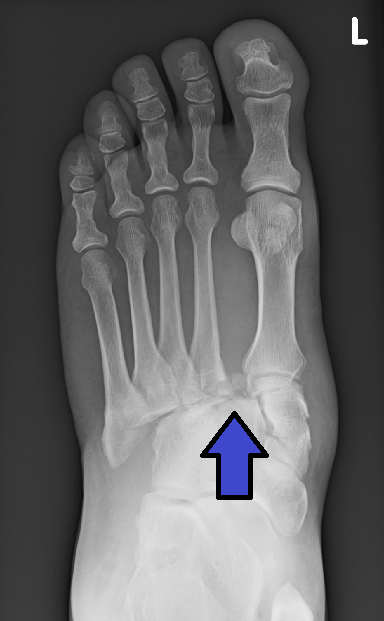

This foot injury is French for a twisting, compressive, axial load to a painful but necessary ortho consult?

Lisfranc injury

tarstmetatarsal fracture/dislocation